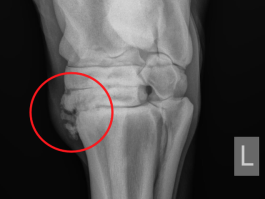

In manchen Fällen lassen sich an einem von Arthrose betroffenen Gelenk bereits von aussen und ohne Röntgenbild Knochenumbauprozesse wie z.B. ein „Spathöcker“ (vgl. Abb.4) oder eine „Schale“ (vgl. Abb.3) erkennen. Nach abgeschlossener Lahmheitsuntersuchung bzw. wenn bekannt ist, welches Gelenk betroffen ist, erfolgt in der Regel eine Röntgenuntersuchung.

Abb. 4: Äusserlich erkennbare knöcherne Auftreibung („Spathöcker“) an der Innenseite der unteren Sprunggelenksreichen links und Röntgenbild rechts.